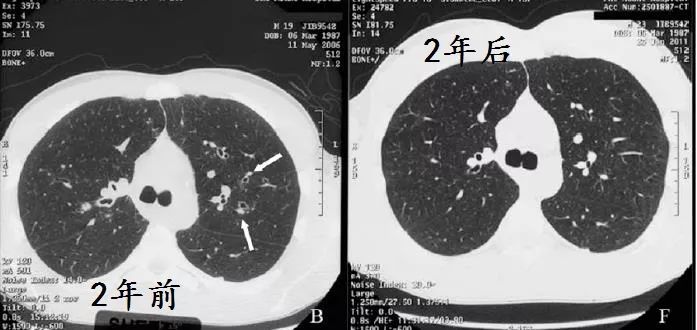

He adhered to treatment and significant improvement in symptoms was noted over 6

months. At a review 2 years later, he had complete resolution of symptoms and further improvement in spirometry values , and repeat high-resolution computed tomography showed no evidence of previously noted dilated airways.

病人坚持治疗,6月后症状好转,2年后,各方面都好转,连支气管扩张都好了!

This case highlights the fact that not all radiological postinfective bronchiectatic changes should be considered as irreversible.Early effective therapy should be provided and the patient monitored for resolution。

事实胜于雄辩,影像学发现的支扩,并不都是不可逆的。早期治疗,随访,有希望缓解。

下面是作者提供的精彩图谱,什么时候,国内的文献也有图,有稍微清晰一点的图。